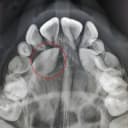

تصویربرداری: برای بررسی دقیق‌تر وضعیت دندان و امکان مشاهده ریشه آن، از تصاویر اشعه ایکس یا سی‌تی‌اسکن استفاده می‌شود و سپس نوع جراحی و مراحل آن تعیین می‌گردد.

جراحی دندان عقل نهفته

زمانی که دندان عقل به صورت کامل از لثه خارج نشود یا به صورت افقی و مورب رشد کند، جراحی دندان عقل ضروری خواهد بود. در این روش، بافت لثه و گاهی بخشی از استخوان فک برداشته می‌شود تا امکان دسترسی و خارج کردن دندان به وجود آید. جراحی دندان عقل نهفته معمولا با بی‌حسی موضعی است و یکی از رایج‌ترین انواع جراحی دندان به شمار می‌آید.

در فهرست انواع جراحی دندان به جراحی کیست دندان می‌رسیم که در صورت رشد کیست، انجام آن ضروری است. کیست‌های دندانی معمولا در اطراف ریشه‌های عفونی یا دندان‌های نهفته شکل می‌گیرند و رشد آن‌ها می‌تواند موجب آسیب به استخوان فک شود. در طی این جراحی، کیست همراه با بافت اطراف آن کاملا برداشته می‌شود و سپس ناحیه را ضدعفونی می‌کنند و بخیه می‌زنند. مراقبت‌ها و معاینه‌های دندانپزشک پس از جراحی کیست دندان اهمیت زیادی دارد تا از عود کردن کیست جلوگیری شود.